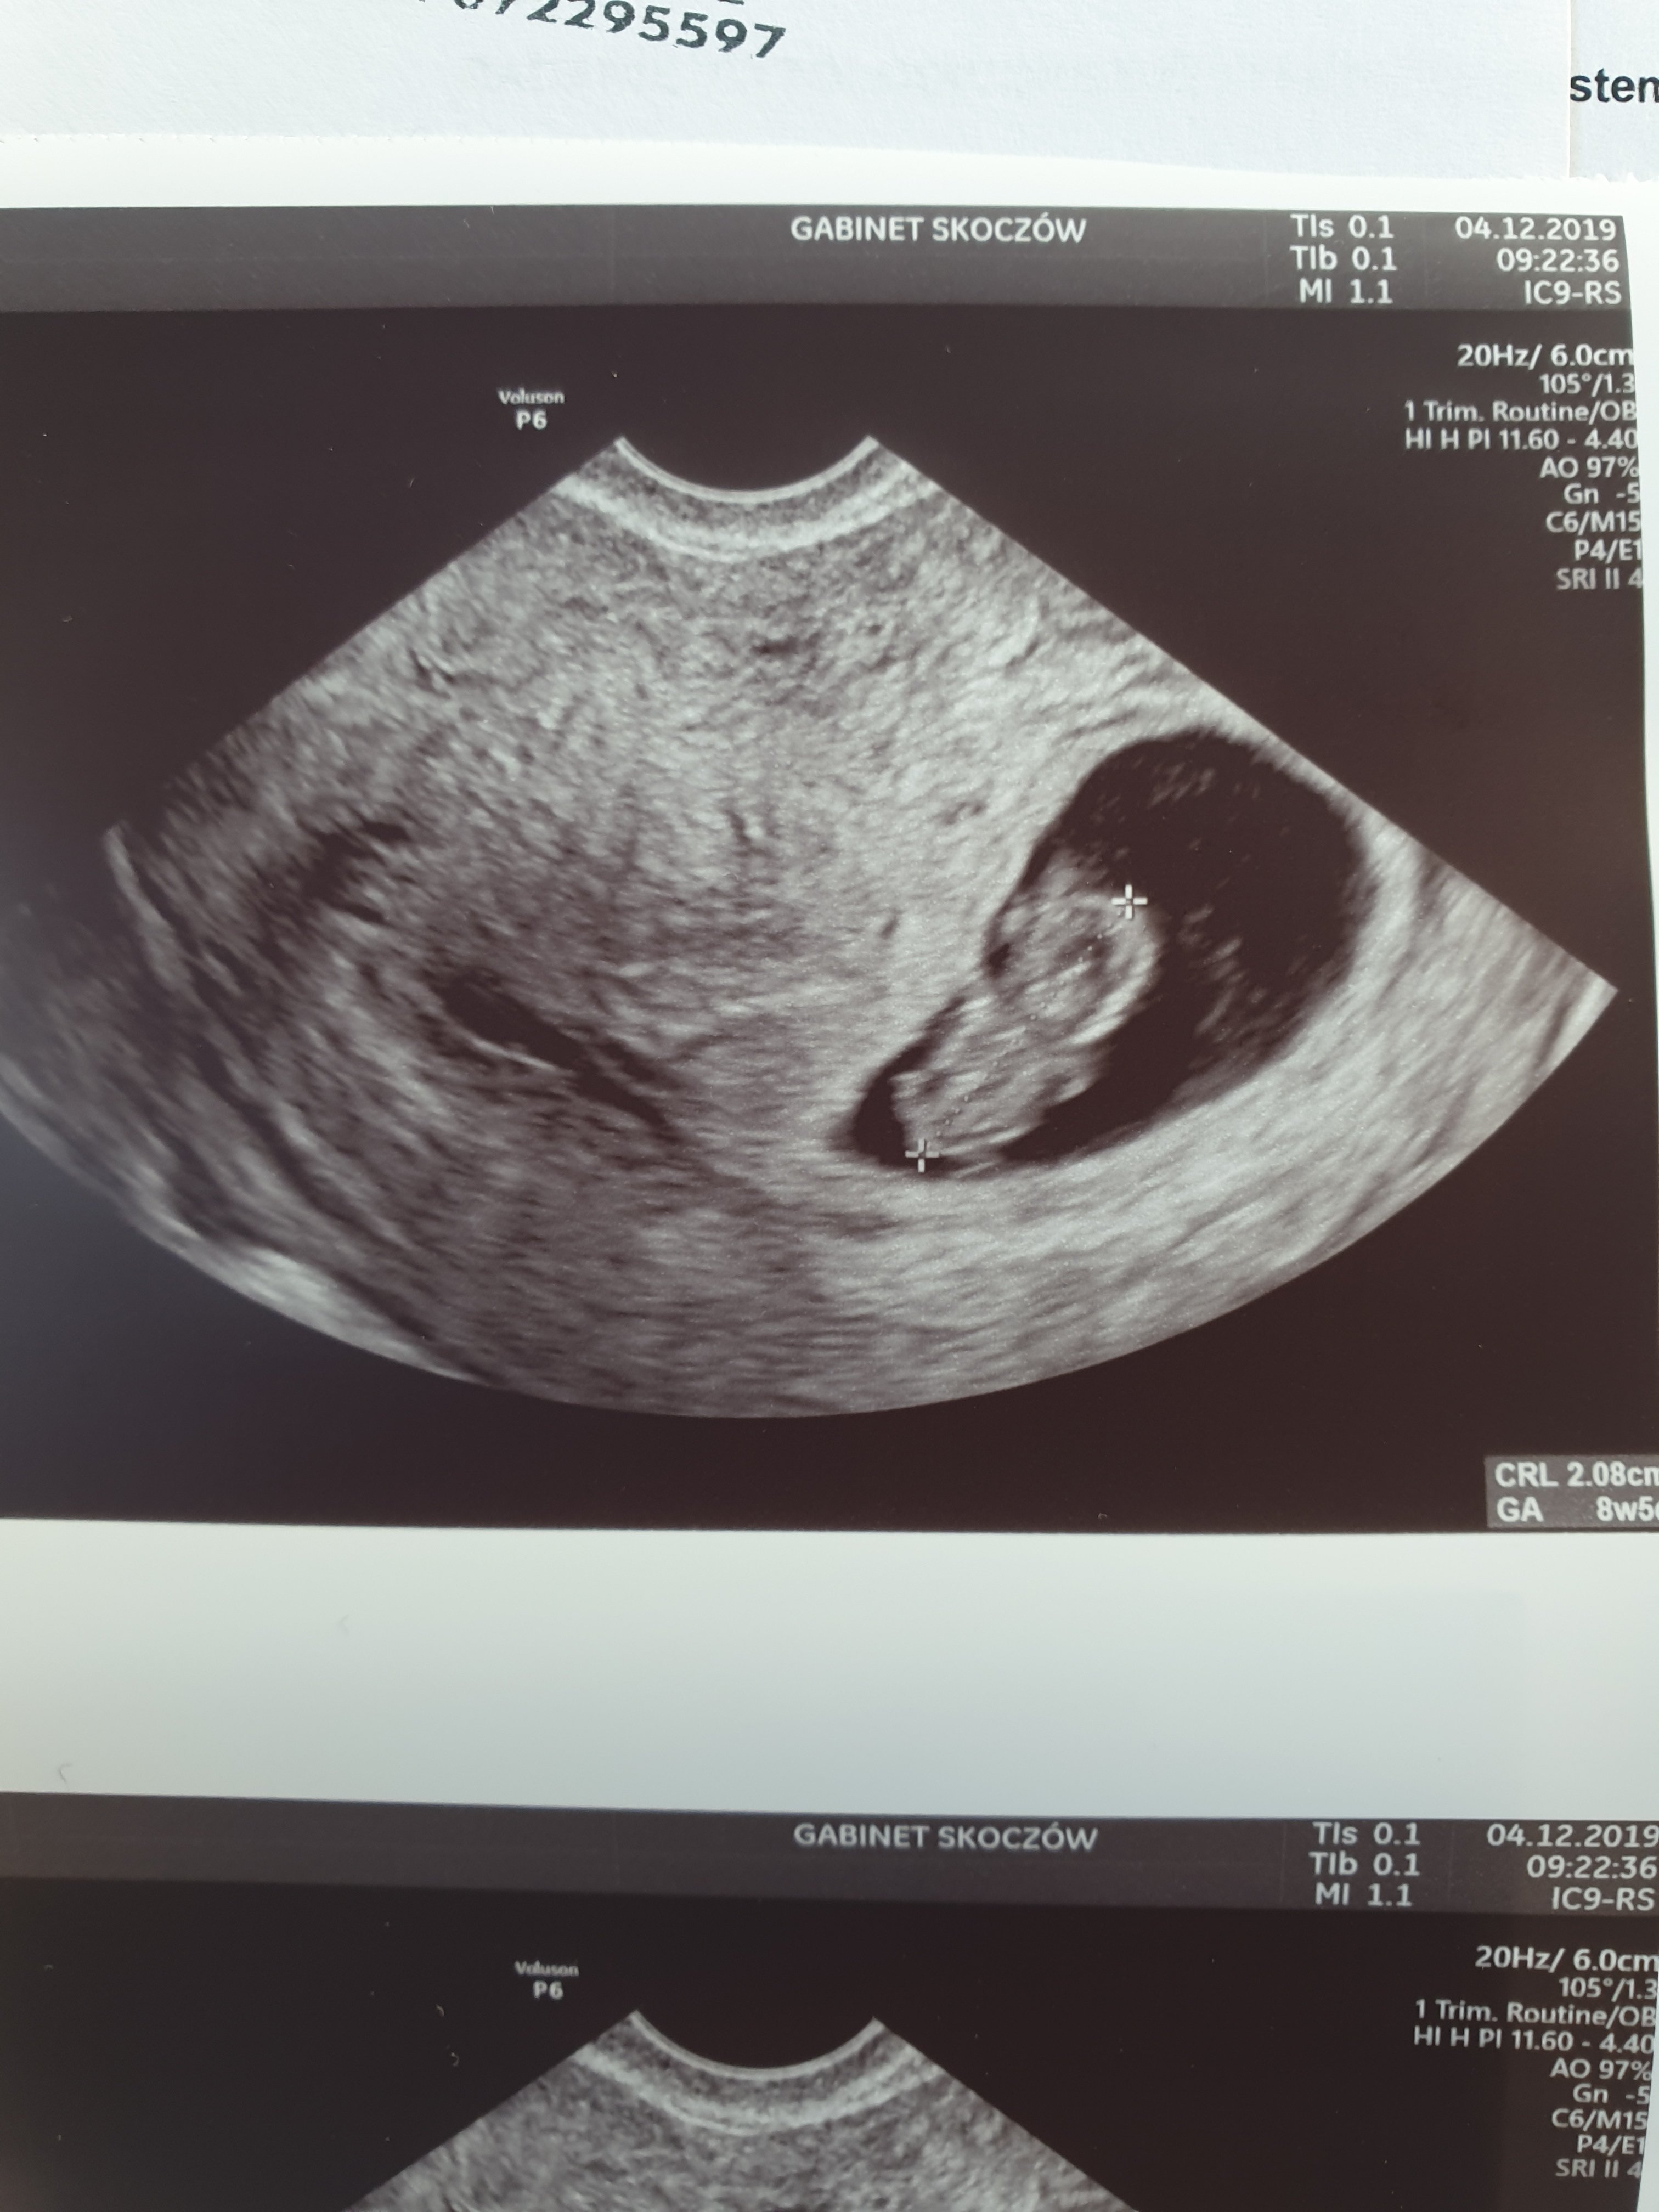

Załączniki

• 20191204_111527.jpg

20191204_111527.jpg

825,9 KB · Wyświetleń: 121

• 20191204_111534.jpg

20191204_111534.jpg

807,7 KB · Wyświetleń: 124

Hmm mi z flo wychodzi 9td4 mija się z usg około 2 dni wiec jest super ale mierząc powiedziała mi 2 cm wszystko Oki rączki nóżki główka serduszko heh i dupcia bo akurat tak się ustawiło